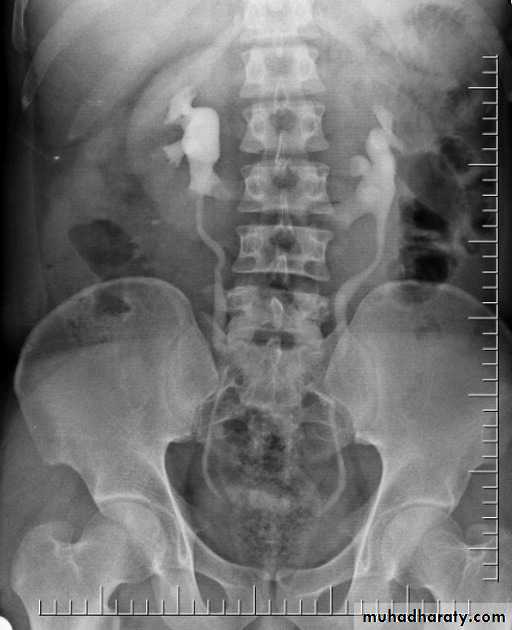

Bilateral ureteroceles. dilatation of the distal ureter as it enters through the bladder wall. This produces a typical “cobra head” deformity (arrows.